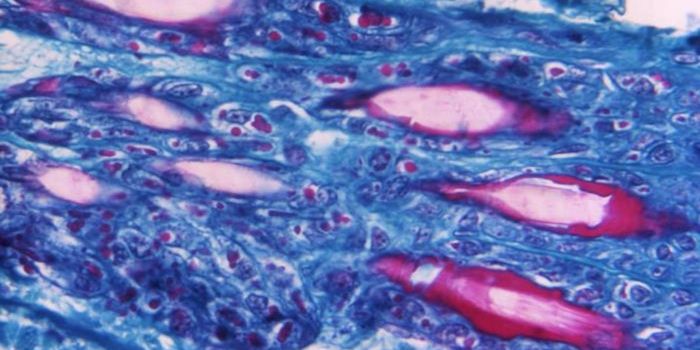

DEC 28, 2021ImmunologyAncylostoma caninum, a type of hookworm, attached to the intestinal mucosa. Image via Wikimedia Commons. Hookworms are b ...